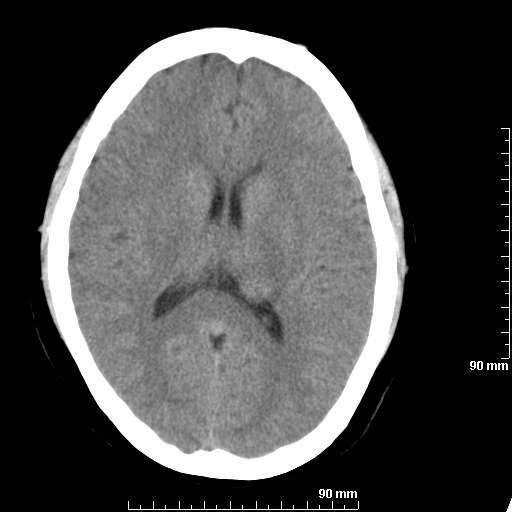

我院西门子单排CT由于一零件受损而产生的伪影.

哈哈,都不是。是虑线器fiter裂损。大家没想到吧。

哦,跟脑出血有点像哦

形状不规则,边缘模糊。比较特殊的一种伪影哈!

这种伪影很常见!伪影应该是在视野的中心的。

西门子的虑线器fiter裂损这才是很难见的问题,GE的最常见

虑线器老化,中间崩裂一块掉了